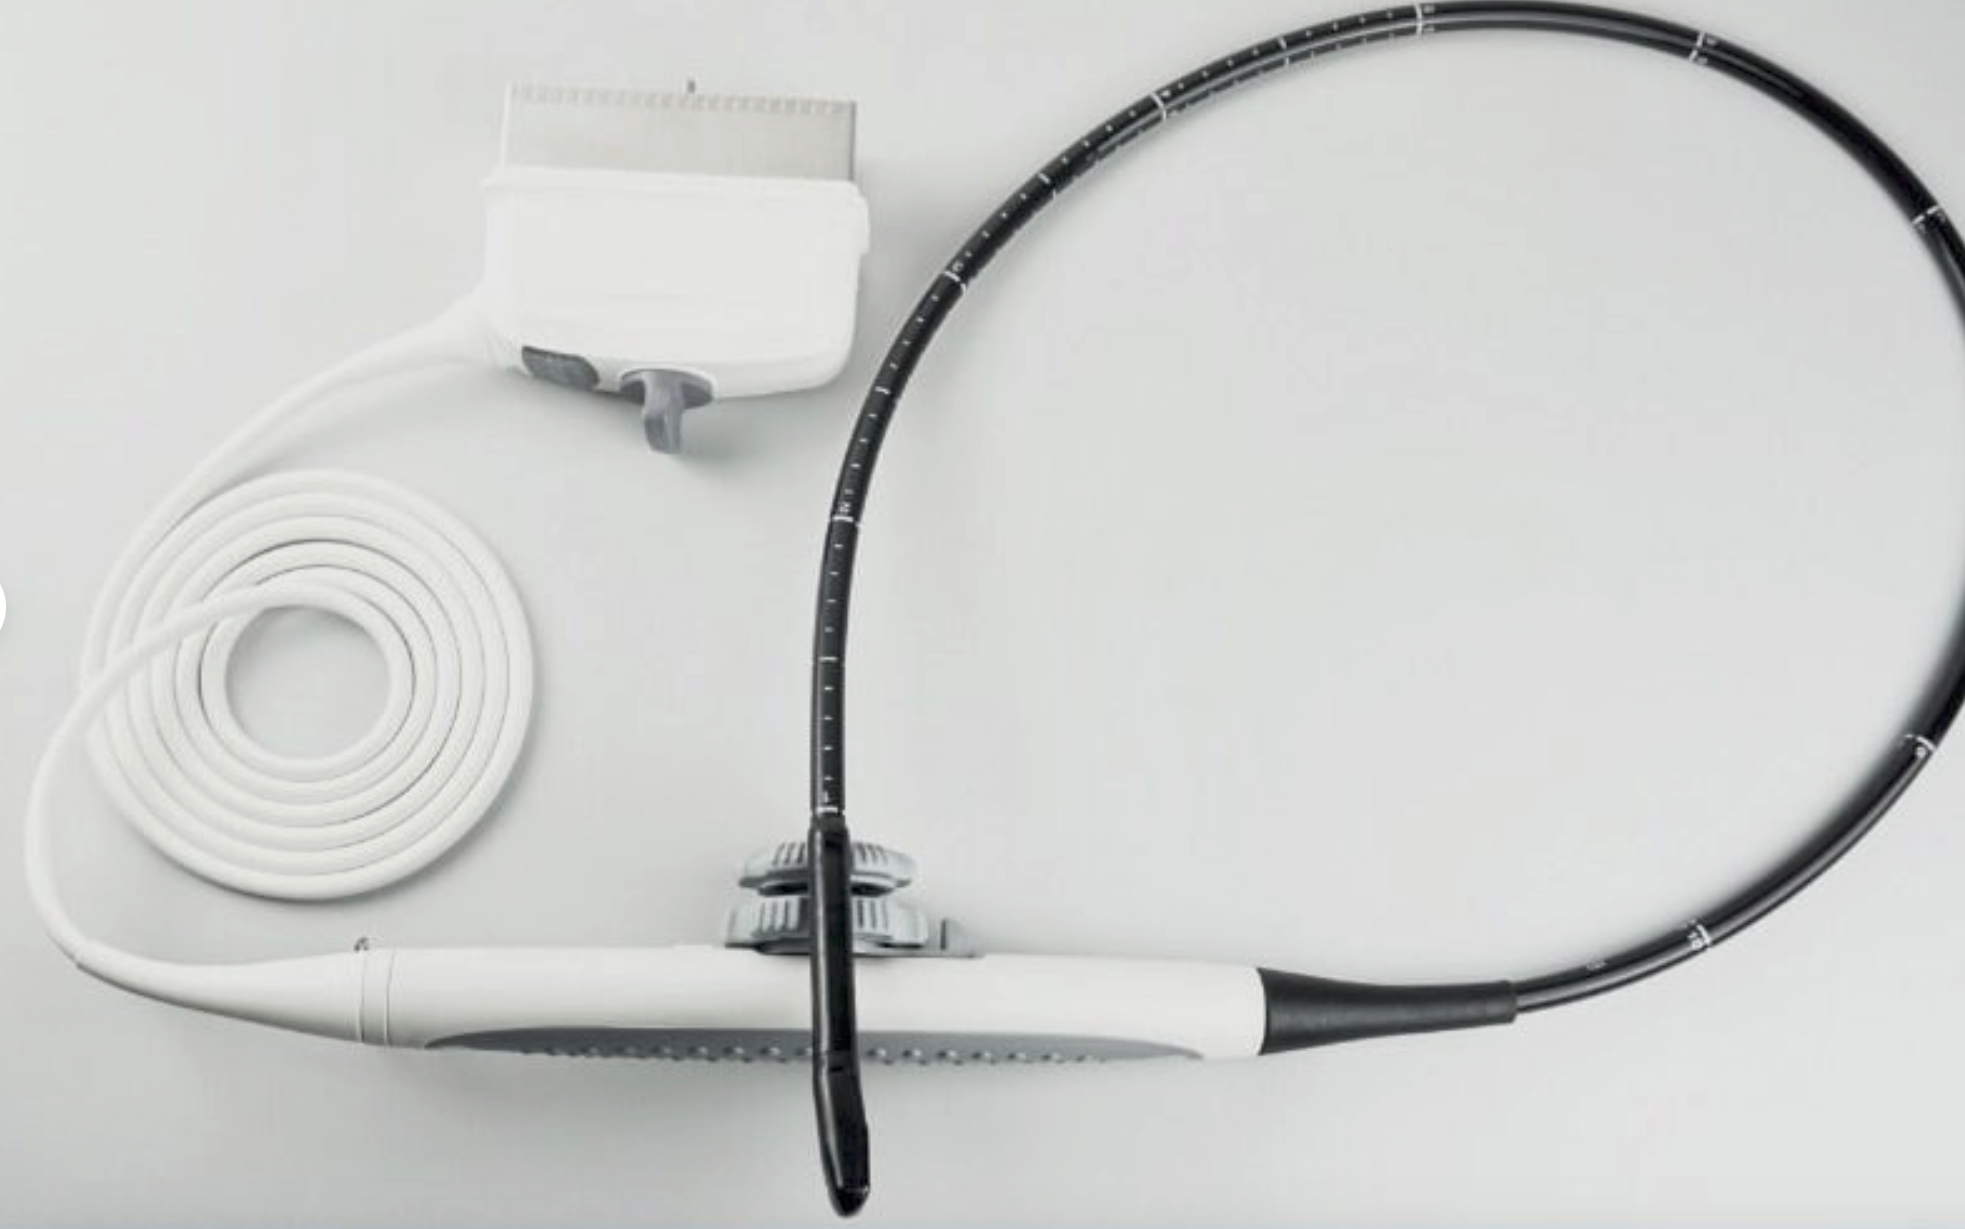

The Sonosite M-Turbo Portable is compatible with a wide range of probes and transducers, enhancing its versatility across various medical disciplines. Whether it's for abdominal imaging, vascular assessments, or musculoskeletal evaluations, this ultrasound machine delivers precise and dependable images. Moreover, the device supports advanced imaging modes such as Color Doppler, M-Mode, and Power Doppler, providing comprehensive diagnostic options for practitioners.